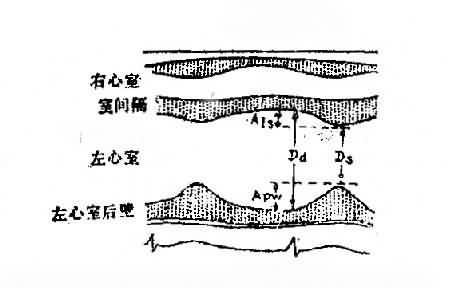

此是利用超声扫描技术 在荧光屏上显示超声波通过心脏各层结构如;心包、心肌、心内膜、室间隔、瓣膜和主动脉时发生的反射,借以观察心脏与大血管的搏动情况、房室的舒张和瓣膜开关的活动规律。目前常用的M型、B型超声心动图对二尖瓣、主动脉瓣的狭窄和关闭不全、三尖瓣狭窄,二尖瓣脱垂,特发性肥厚性主动脉瓣下狭窄,心房粘液瘤,心包积液,房、室间隔缺损等的诊断均有较大的价值。此外,利用超声心动图测量房、室腔的大小,计算心排出量、射血分数等以了解左心室功能。近年来应用彩色多普勒血流显像探查瓣膜关闭不全的返流和先心病的分流量、提高了疾病诊断质量。(图3-1-4图3-1-5)

图3-1-4 超声心动图测量左心室功能各项指标示意图

Dd:心室舒张期末短轴长度;Ds:左心室收缩期末短轴长度;Apw:左心室后壁运动幅度;AIS室间隔运动幅度